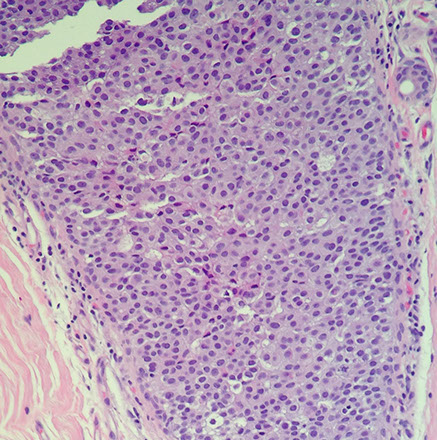

Ductal Carcinoma in situ (DCIS)

Has widely variable features, but similar to ADH have neoplastic cells confined to ducts and lobules

Most present as microcalcifications

- 30% present radiographically as soft tissue density +/- calc or as architecturally altered

-- few present as a mass, Paget's dz, or another abnormality

Historically grouped into comedo, cribriform, micropapillary, papillary, and solid types

- now grouped into 3 grades based on nuclear features and necrosis

Things to look for: nuclear grade, necrosis, polarization, architecture

Low grade

Small, well-defined membranes; uniform; homogenous chromatin and inconspicuous nucleoli

- slightly inc N:C; few mits; +/- hyperchromasia

Cells polarize around cribriform lumens

Rarely has comedo necrosis

IHC: Diffuse strong ER / PR; low prolif rate; no HER2 amp; membranous p120, negative CK5/6

- ER status only thing used clinically (for tamoxifen tx)

loss of 16q and 17p; gain at 1q

Tx: complete local eradication and rads (at current location)

- assoc c 10x risk invasive ca in same breast (vs bilat in ADH)

Intermediate grade lies somewhere bwt Low and High grade

High grade

Large, pleomorphic nuclei; vesicular / coarse chromatin; frequent mits and comedo necrosis

- cells may not appear too organized (like UDH?)

Stroma surrounding lesion c inc vessels

Commonly have mutated p53, causing p53 to accumulate

Sometimes may have a few (+) CK5/6 cells

Loss at 11q; 14q; 8p and 13q; gains at 17q, 8q and 5p